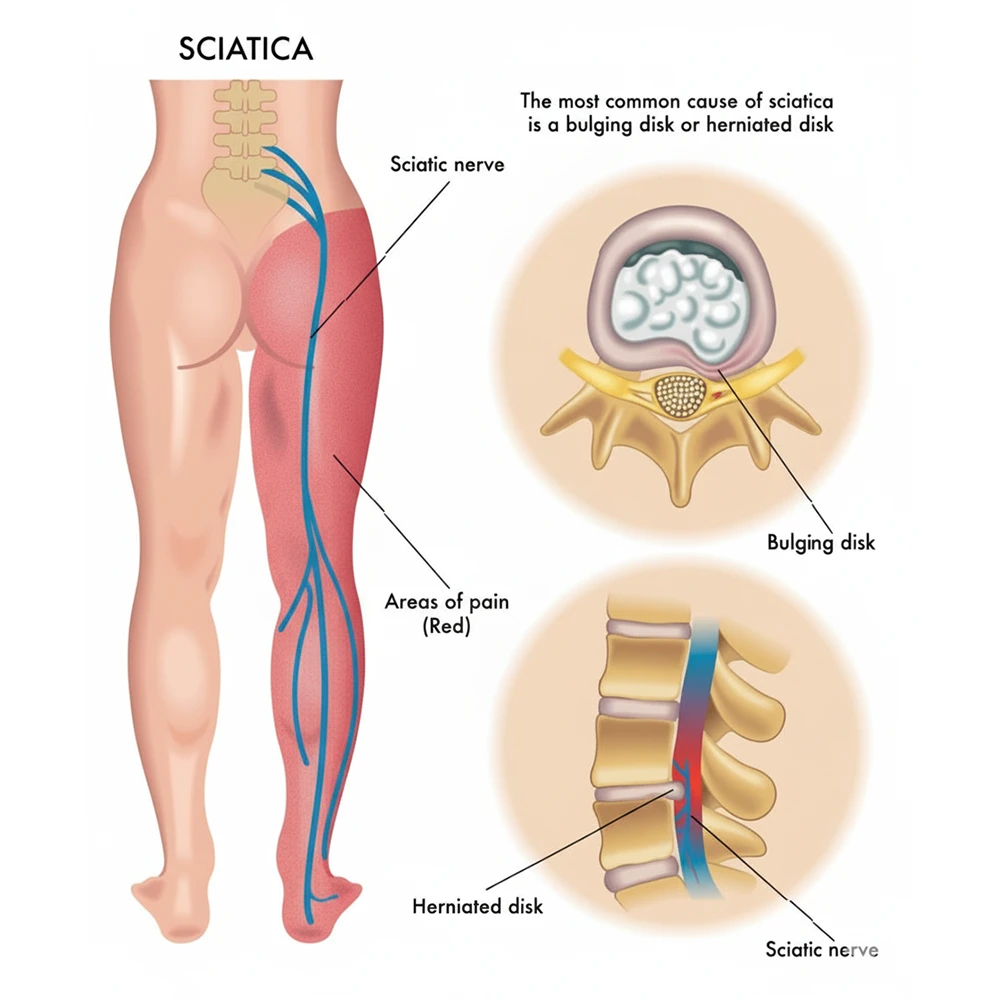

Sciatica Pain

Sciatica pain happens when the sciatic nerve gets pressed or irritated. The pain starts in the lower back and can travel to the hips, buttocks, and legs. It often feels sharp, burning, or shooting. With proper care and therapy, this pain can be reduced and managed.